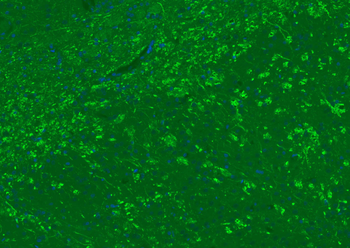

Paraformaldehyde-fixed, paraffin embedded (rat brain), Antigen retrieval by boiling in sodium citrate buffer (pH6.0) for 15 min, Blocking buffer (normal goat serum) at 37°C for 30 min, Antibody incubation with (MBP) Polyclonal Antibody, Unconjugated (orb783422) at 1:200 overnight at 4°C, followed by a conjugated Goat Anti-Rabbit IgG antibody for 90 minutes, and DAPI for nuclei staining.